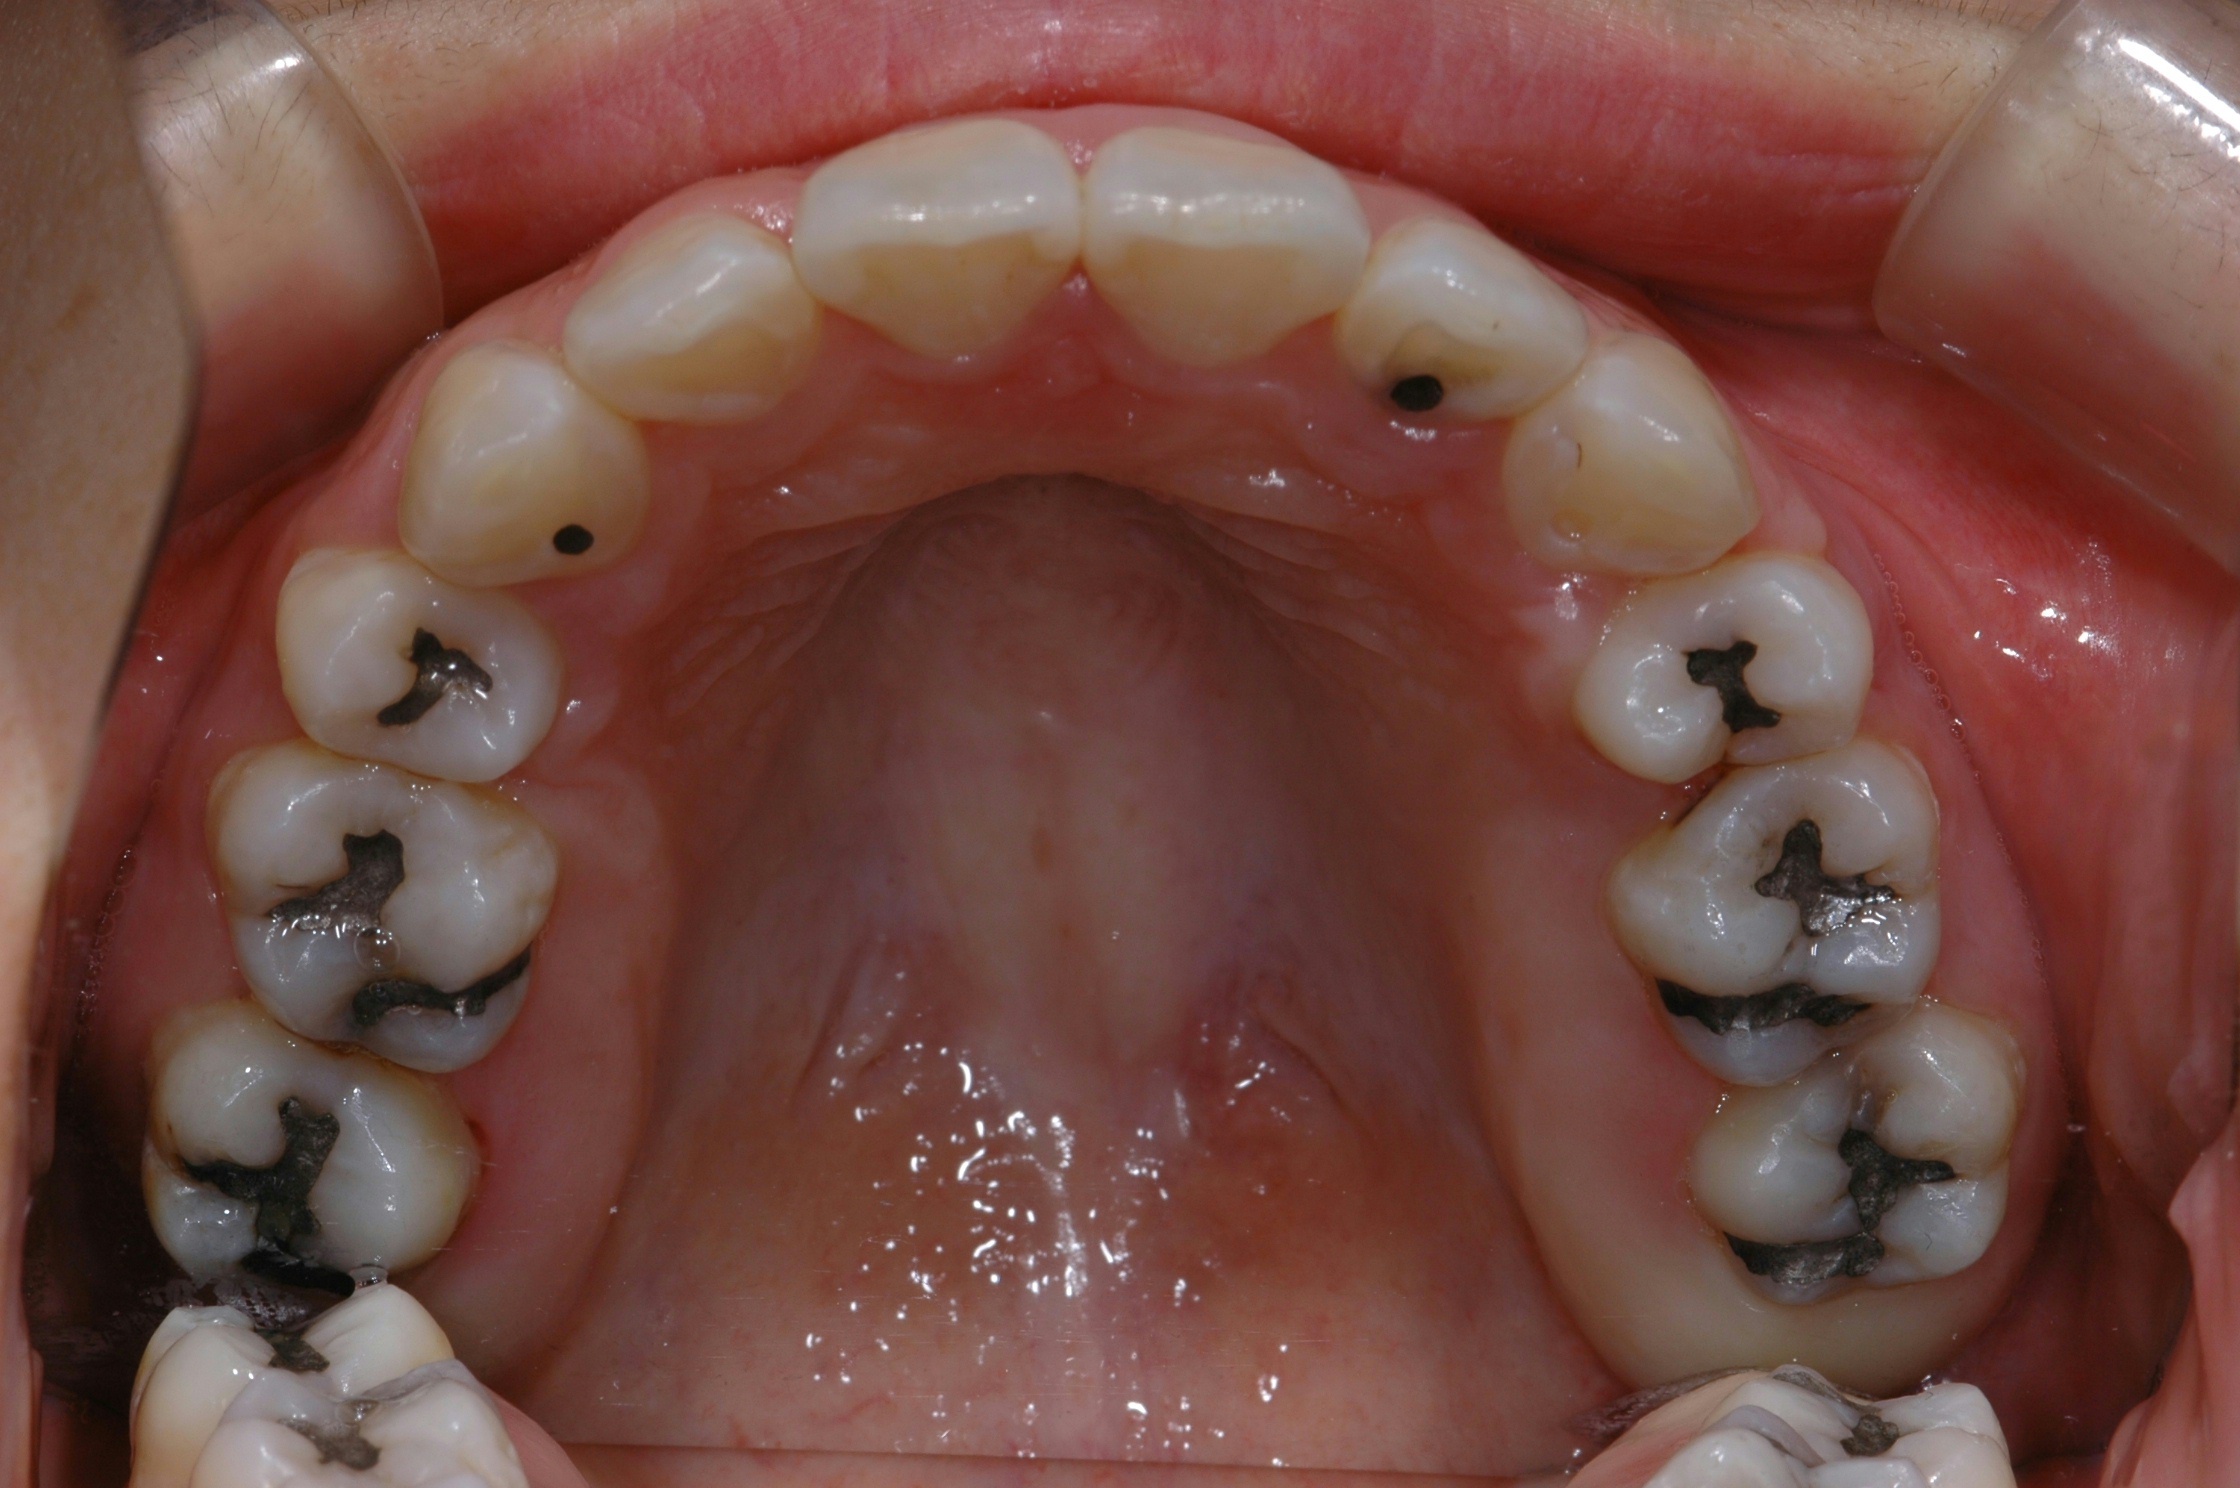

치료 후 사진입니다.